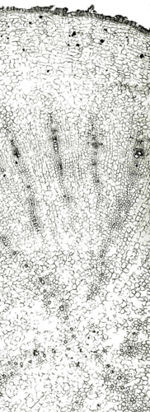

本品は細長い円柱形~紡錘形を呈し、しばしばなかほどから2~5本の側根を分枝し、長さ5~20cm、主根は径0.5~3cm、外面は淡黄褐色~淡灰褐色を呈し、縦じわ及び細根の跡がある。根頭部はややくびれて短い根茎を付けることがある。折面はほぼ平らで、淡黄褐色を呈し、形成層の付近は褐色である。 本品は特異なにおいがあり、味は初めわずかに甘く、後にやや苦い。 皮層に樹脂道が、同心円状に断続した環状を示している。形成層は明瞭で、木部の道管はほぼ単列に放射状に配列している。髄は認められない。 ほとんどのウコギ科の植物には、シュウ酸カルシウムの集晶があり、トチバニンジン属(Panax属)においてもすべて認められる。 |

内部形態は基本的に類似し、中国産,韓国産の産地による違いはほとんど認められない。 日本産(信州産)のみ、道管が幾分集合していて単列の乱れが見られる。

| 生干人参<日本・信州> | 生干人参<中国黒竜江省> | 生干人参<韓国> | 曲参<韓国> |